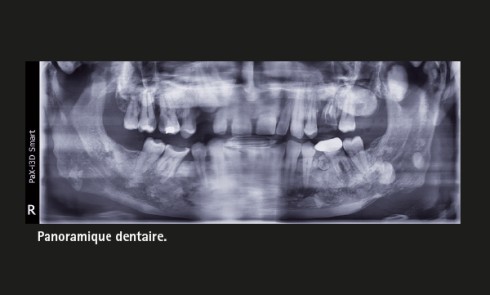

Tony D, 37 ans, est adressé par son chirurgien-dentiste traitant pour avis sur des lésions ostéo-condensantes multiples des maxillaires découvertes...